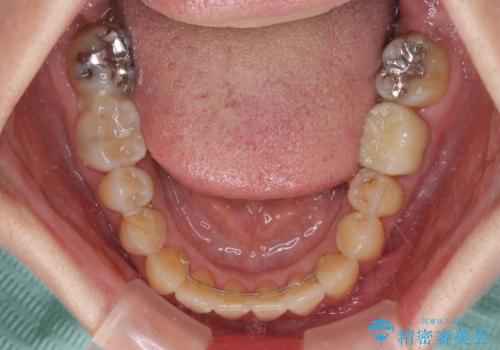

骨格的に下顎が前方位にありますが、歯列矯正で前歯の被蓋関係を改善することができると判断されたため、インビザラインにより矯正治療を行うこととしました。

また、上顎前歯と下顎大臼歯に神経を取り除いた歯があったため、矯正治療後に、セラミッククラウンにて補綴することとしました。

矯正治療中に上顎前歯が下顎前歯を乗り越える際は、前歯でしか咬めない状況が続くため、食事など不便を感じましたが、治療後には前歯の痛みもなくなり、安定した咬み合わせとなりました。